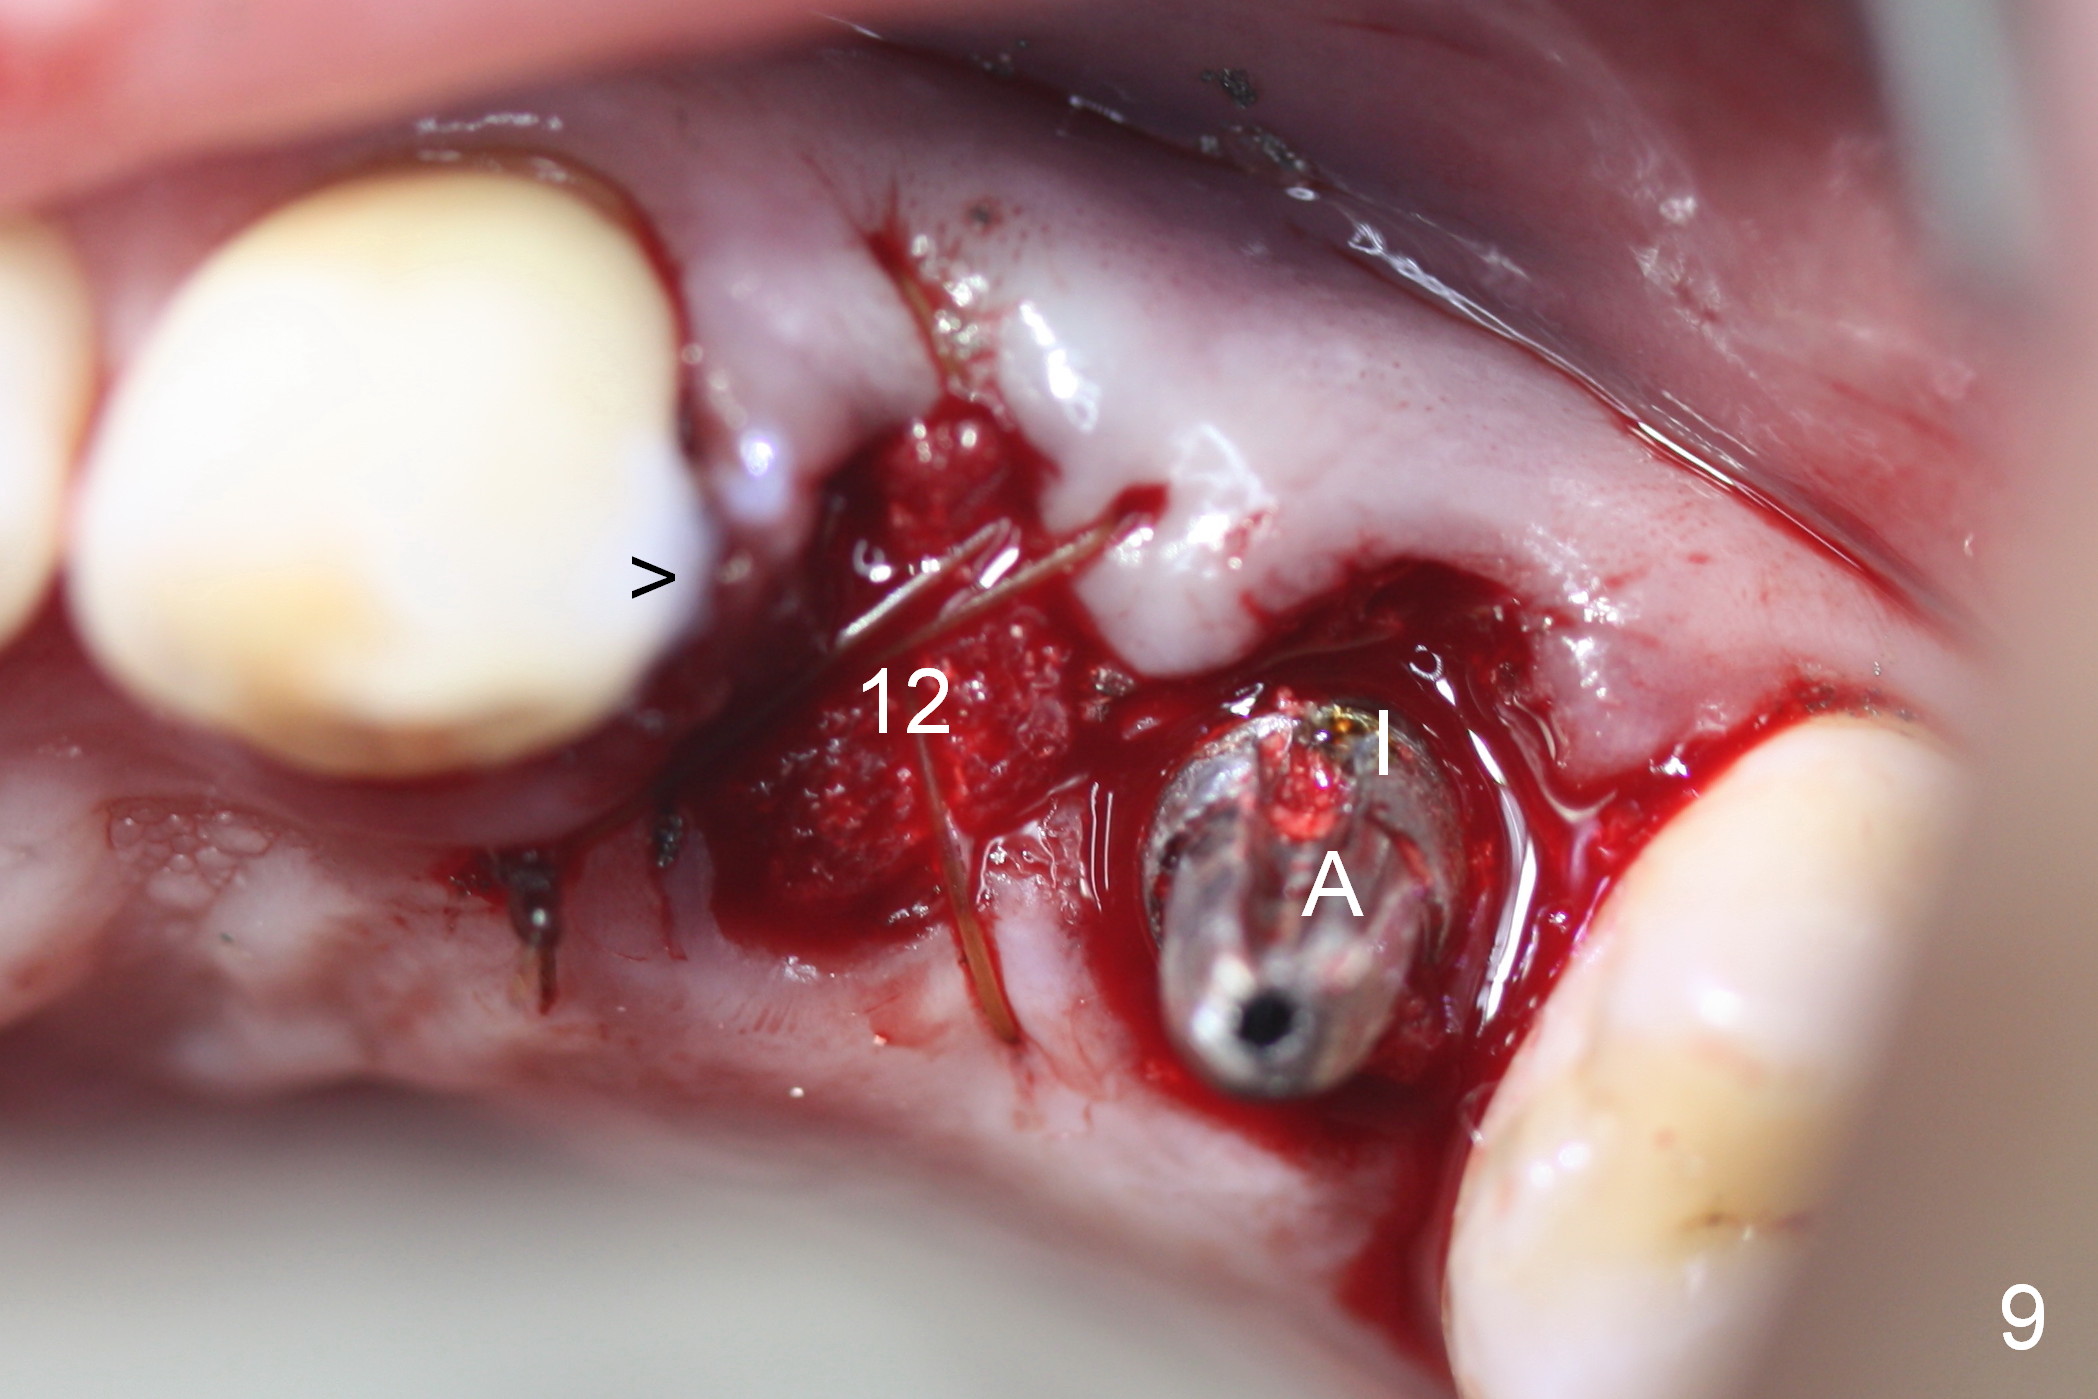

Taking 2 additional PAs with sensor 1 is frustrating (Fig.1,2), no apices shown.  Osteotomy is done smoothly with 2 mm pilot drill at 20 mm, 2.5 mm reamer at 17 mm, and 3 mm reamer at 14 mm and 4.5x20 mm tap at 17 mm.  The 1st intraop PA is taken with sensor 1 when 2 of 4.5x20 mm implants are placed (Fig.3); the implant at #12 is close to the root of the tooth #11.  The 2nd PA is taken with sensor 2: the apex of #11 touches the implant at #12 (Fig.4).  There is no separation when panoramic X-ray is taken (Fig.5).  Effort is exerted to re-direct the osteotomy twice (Fig.6: tap; Fig.7: implant) without success.  When the implant is removed, a PA is taken; it appears that the root of the tooth #11 has no damage (Fig.8).  To obtain the best recovery, socket preservation is carried out with 50/50 cortical/cancellous allograft mixed with Osteogen (Fig.12 *) and Collagen Dressing (Fig.9: #12).  A 2 (or 3)-unit provisional bridge (Fig.10: #12,13) is fabricated over the implant (Fig.9 I)/abutment (A) to cover these 2 sockets.  After acid etching #11 D surface (Fig.9 >) and relining (Fig.11 *), the provisional bridge is bonded to the tooth #11 (Fig.11,12 black >) so that bone graft will be less likely dislodged.